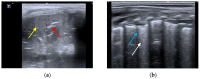

Lung ultrasound (LUS) is, at present, a standard technique for the diagnosis of acute lower respiratory tract infections (ALRTI) and other lung pathologies. Its protocolised use has replaced chest radiography and has led to a drastic reduction in radiation exposure in children. Despite its undeniable usefulness, there are situations in which certain quantitative measurements could provide additional data to differentiate the etiology of some pulmonary processes and thus adapt the treatment. Our research group hypothesises that several lung processes such pneumonia may lead to altered lung tissue stiffness, which could be quantified with new diagnostic tests such as lung sono-elastography (SE). An exhaustive review of the literature has been carried out, concluding that the role of SE for the study of pulmonary processes is currently scarce and poorly studied, particularly in pediatrics. The aim of this review is to provide an overview of the technical aspects of SE and to explore its potential usefulness as a non-invasive diagnostic technique for ALRTI in children by implementing an institutional image acquisition protocol.